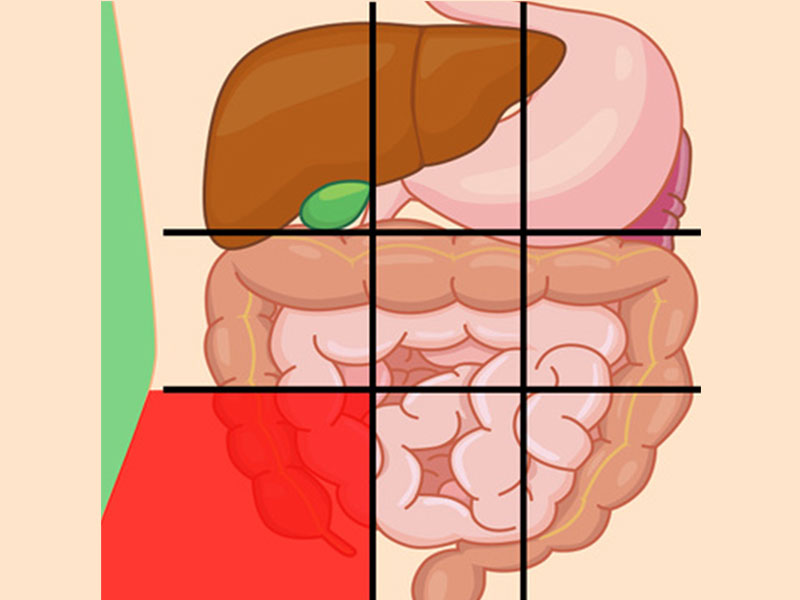

درد شکم در نواحی مختلف نشانه چیست؟

محل درد در شکم ممکن است سرنخی برای علت آن درد باشد که در زیر به بررسی آنها میپردازیم:

درد شکم سمت چپ پایین نشانه چیست؟

این بخش شامل روده بزرگ است، پس اگر مشکلی برای این اندام پیش بیاید، در این بخش احساس درد میکنید.

علل شایع درد این ناحیه عبارتاند از:

- بیماری کرون

- سندرم روده تحریکپذیر

- سرطان

- عفونت کلیه

- کیستهای تخمدان

- آپاندیس

درد پایین شکم نشانه چیست؟

این بخش شامل اندامهای تناسلی و مثانه میباشد.

مشکلاتی که ممکن است باعث در پایین شکم شوند از جمله:

- آپاندیسیت

- انسداد روده

- حاملگی خارج رحمی

- کیستهای تخمدان

- عفونت مثانه